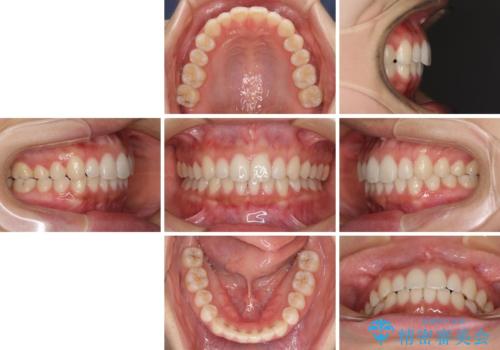

海外勤務中でも矯正治療 インビザラインによる軽度叢生改善

- 前歯のデコボコを気にして来院された患者様です。

通常であれば半年から10ヶ月程度で終了する歯並びでしたが、海外に長期出張することになったため、1年10ヶ月の期間を要しました。

出張に行かれてしまうと追加のマウスピースを発注できないため、マウスピースの交換頻度を低くし、一時帰国のタイミングに合わせていくことで、スムーズに進めて行くことができました。